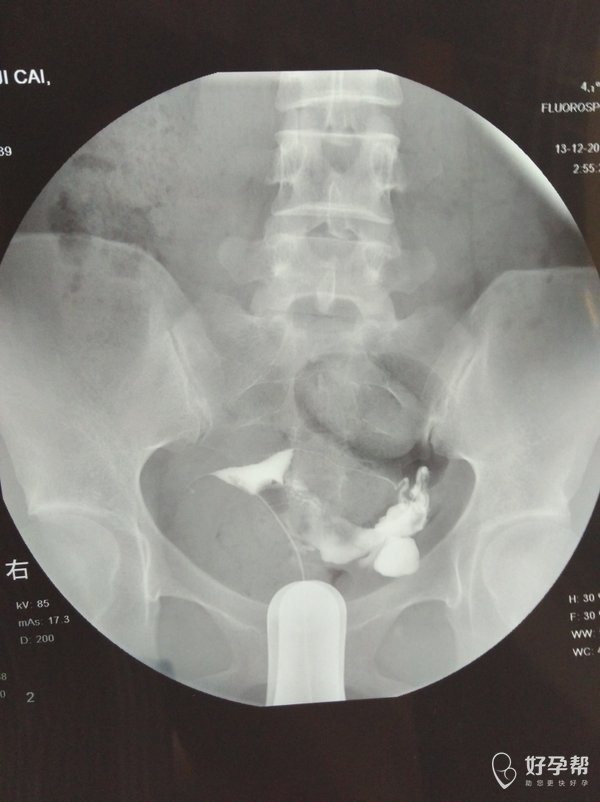

输卵管通而不畅应该怎么治疗

你好,可以考虑输卵管通液,理疗,及中药治疗。

麻烦医生指点,输卵管通而不畅要怎么治疗?我的右侧输卵管部分切除,所有希望都寄托在这跟管上了,我不想试管,想自然怀孕,帮帮忙指点

,谢谢!从哪里看的出通而不畅的,也帮忙指点一下